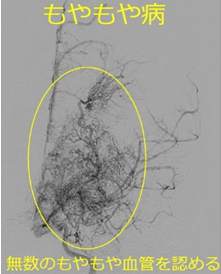

脳血管障害は大人に多い疾患ですが、小児でも脳梗塞や脳出血、くも膜下出血を起こすことがあります。代表的な小児脳血管障害であるもやもや病についてご紹介します。

もやもや病とは、脳の血管が進行性に狭窄する原因不明の疾患です。その付近に側副血行路が発達して脳血管撮影検査でもやもやと描出されるため、もやもや病と名付けられています。

治療としては、脳血流が著しく不足している場合には血行再建術を行います。術式にはいろんなバリエーションがあります。大きく分けて、①直接的血行再建術(浅側頭動脈(STA)-中大脳動脈(MCA)バイパス術など)と、②間接的血行再建術(浅側頭動脈、側頭筋、骨膜などを脳表に接着させ血管新生を促すもの)があります。当科では患者さんの病態や重症度に応じて、①のみ、②のみ、①と②の組み合わせなど様々な治療を行なっています。